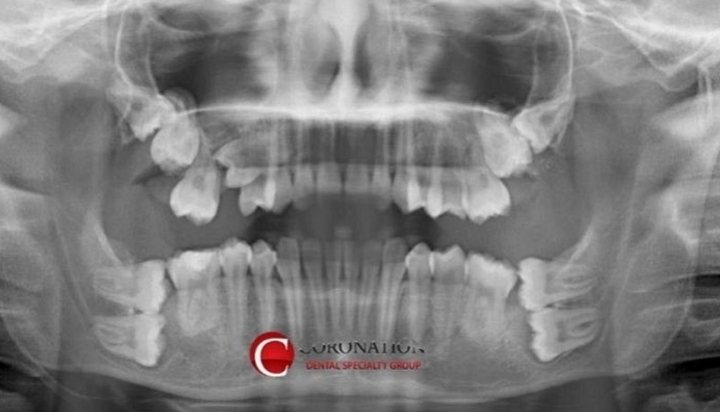

[스크랩] [흥미돋]치과의사 멘붕 빠트린 사랑니 뽑으러 온 환자의 엑스레이 사진

전생에 나라를 팔아먹었나봐요...ㅠㅠ